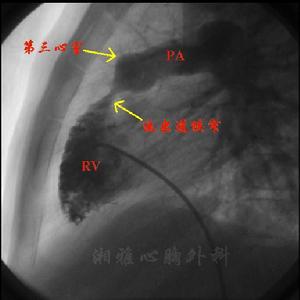

漏斗部狹窄:四聯症病人幾乎都有不同程度的漏斗部狹窄。大多數病例漏斗部狹窄與肺動脈瓣膜狹窄合併存在。漏斗部狹窄是由肥厚的壁束、隔束和室上嵴所造成。漏斗部狹窄與肺動脈瓣之間往往形成大小不等的第3心室。漏斗部狹窄位於右心室流出道遠側,靠近肺動脈瓣者則第3心室小;漏斗部狹窄位於右心室流出道近端則第3心室腔大,並有纖維環狀入口。有時漏斗部發育不良呈現瀰漫的長而細的管狀狹窄,但無第3心室。

右心導管檢查:右心導管檢查顯示右心室壓力增高,可到達左心室壓力水平。心導管可從右心室直接進入主動脈說明存在心室間隔缺損和主動脈騎跨。由於右心室流出道及/或肺動脈狹窄顯示右心室與肺動脈之間呈現收縮壓力階差。分析壓力曲線形態可判明狹窄的部位、類型和有無第3心室。動脈血氧飽和度降低;一般在89%以下,運動後進一步降低。

選擇性右心室造影檢查:法樂四聯症病例決定手術治療之前必需作選擇性右心室造影術。於右心室腔內放入心導管注射造影劑,連續X線拍片檢查可顯示肺動脈和主動脈同時顯影和主動脈騎跨程度,與此同時造影劑從右心室經心室間隔缺損進入左心室。造影檢查尚能顯示右心室流出道及/或肺動脈狹窄的部位和程度,了解肺動脈發育情況和測量肺動脈總乾和升主動脈的直徑,計算兩者的比值。